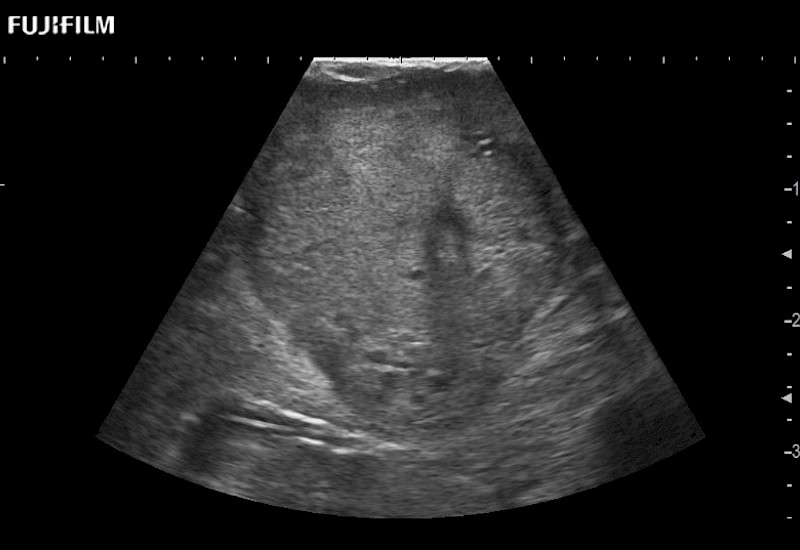

The ARIETTA 750 incorporates all of the proven technologies and functions that medical professionals have come to expect from Fujifilm Healthcare.

ARIETTA 750 is the definitive diagnostic ultrasound solution for any clinical setting - Private Office, Imaging Center, or Hospital. The ARIETTA platform provides the ultimate in clinical performance with its state-of-the-art features and large user-friendly display.

The ARIETTA 650 DI combines trusted Fujifilm Healthcare technologies and features tailored for surgical oncology.

Designed to meet the demands of surgeons, the ARIETTA 650 DI offers precise guidance. Its advanced capabilities and large, intuitive display offer accurate and efficient care in operating rooms and specialized surgical settings.